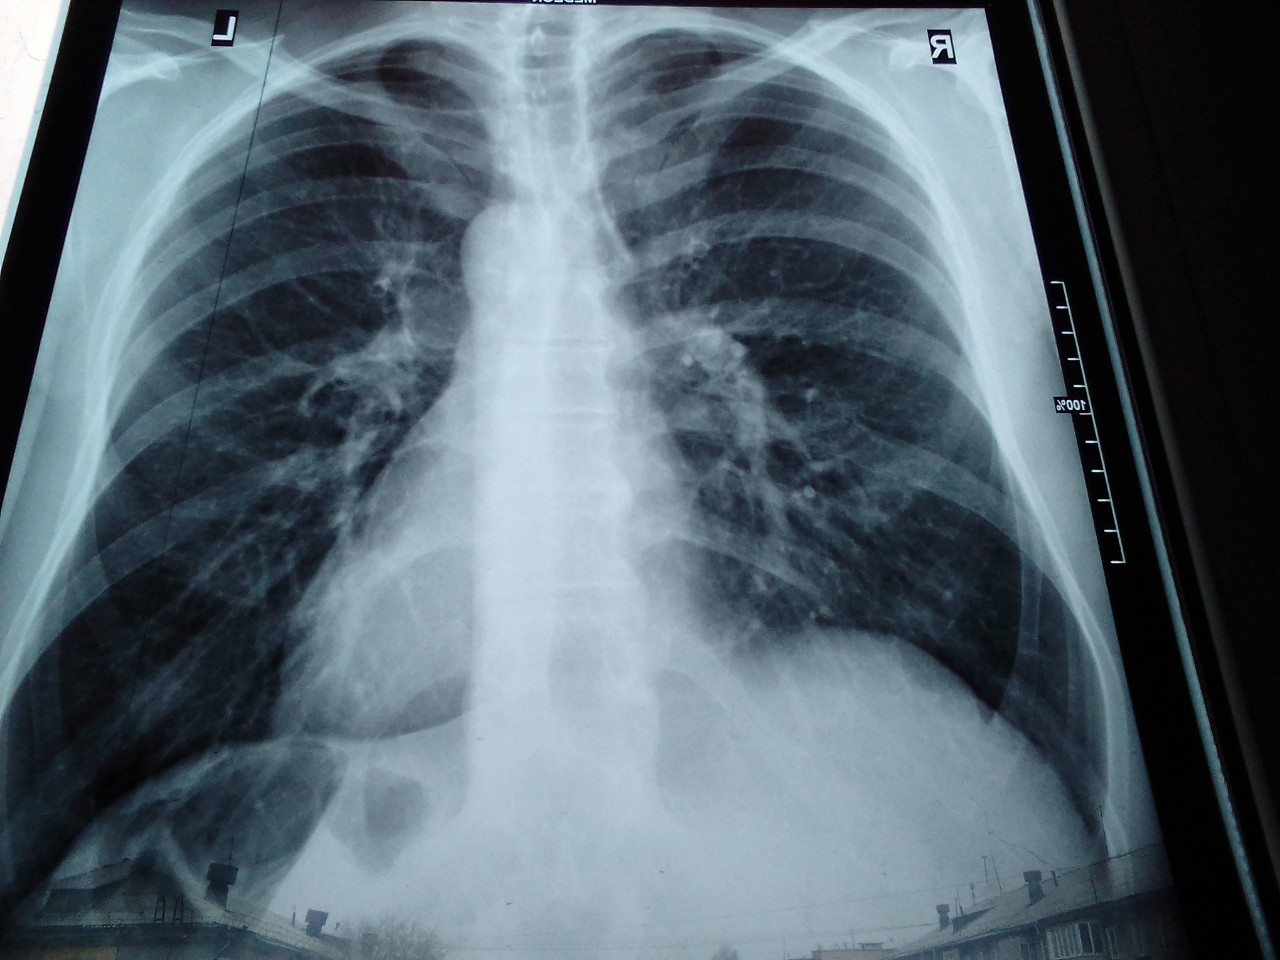

Рентген здоровых легких: примеры снимков и советы

Раздел: Сокровищница опыта